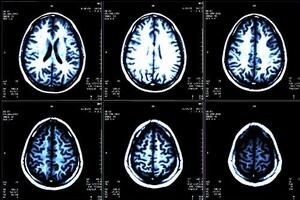

Diabetes can have an impact on your whole body. Your brain is no exception. Recent studies have linked type 2 diabetes to a slowdown in mental functioning and an increased risk of Alzheimer’s disease. The chance of brain complications is just one more reason to keep your diabetes under control.

Scientists are still unsure exactly how type 2 diabetes might affect the brain. However, multiple factors are probably involved.

“High blood sugar may directly affect either nerve cells or support cells in the nervous system,” says Alan Jacobson, M.D., emeritus professor of psychiatry at Harvard Medical School. “It can also lead to damage in both large and small blood vessels.” This, in turn, reduces the

amount of oxygen reaching the brain. Plus, it increases the risk of having a stroke, which can kill brain cells.

In addition, type 2 diabetes usually begins with insulin resistance, in which fat, muscle, and liver cells aren’t able to use insulin effectively. At first, the pancreas responds by pumping out more insulin. The same enzyme that breaks down insulin also breaks down a protein called beta-amyloid, which builds up abnormally in the brains of people with Alzheimer’s disease. With so much of the enzyme at work breaking down insulin, beta-amyloid might have more chance to accumulate.

Research has linked type 2 diabetes to a decline in mental functioning. One study looked at which mental abilities were hardest hit in middle-aged and older adults with diabetes. The results pointed to neurocognitive speed and executive functioning. “These are thought to be major components of cognitive health,” says researcher Roger Dixon, Ph.D., a psychology professor at the University of Alberta.

Neurocognitive speed refers to how quickly and accurately you respond to situations. It’s a useful gauge of overall BRAIN HEALTH

. Executive functioning refers to the planning, control, and monitoring of your own mental activities. “It’s crucial to success in everyday life,” says Dr. Dixon.

The good news is that the deficits seen in this study were mild. And it’s possible they might be preventable. Dr. Dixon says, “By controlling diabetes through medication and lifestyle changes, people may be able to control or limit its effects on the health of their brains.”